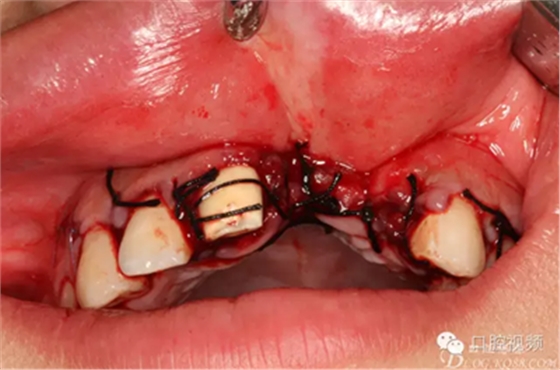

圖10.摘除死骨、并刮除周圍炎性肉芽組織。

圖11.球鉆修整牙槽骨面。

圖12.繼續(xù)清理創(chuàng)面周圍炎性組織

圖13. 清理、沖洗完畢的創(chuàng)面情況

圖14.直接縫合關(guān)閉創(chuàng)面。